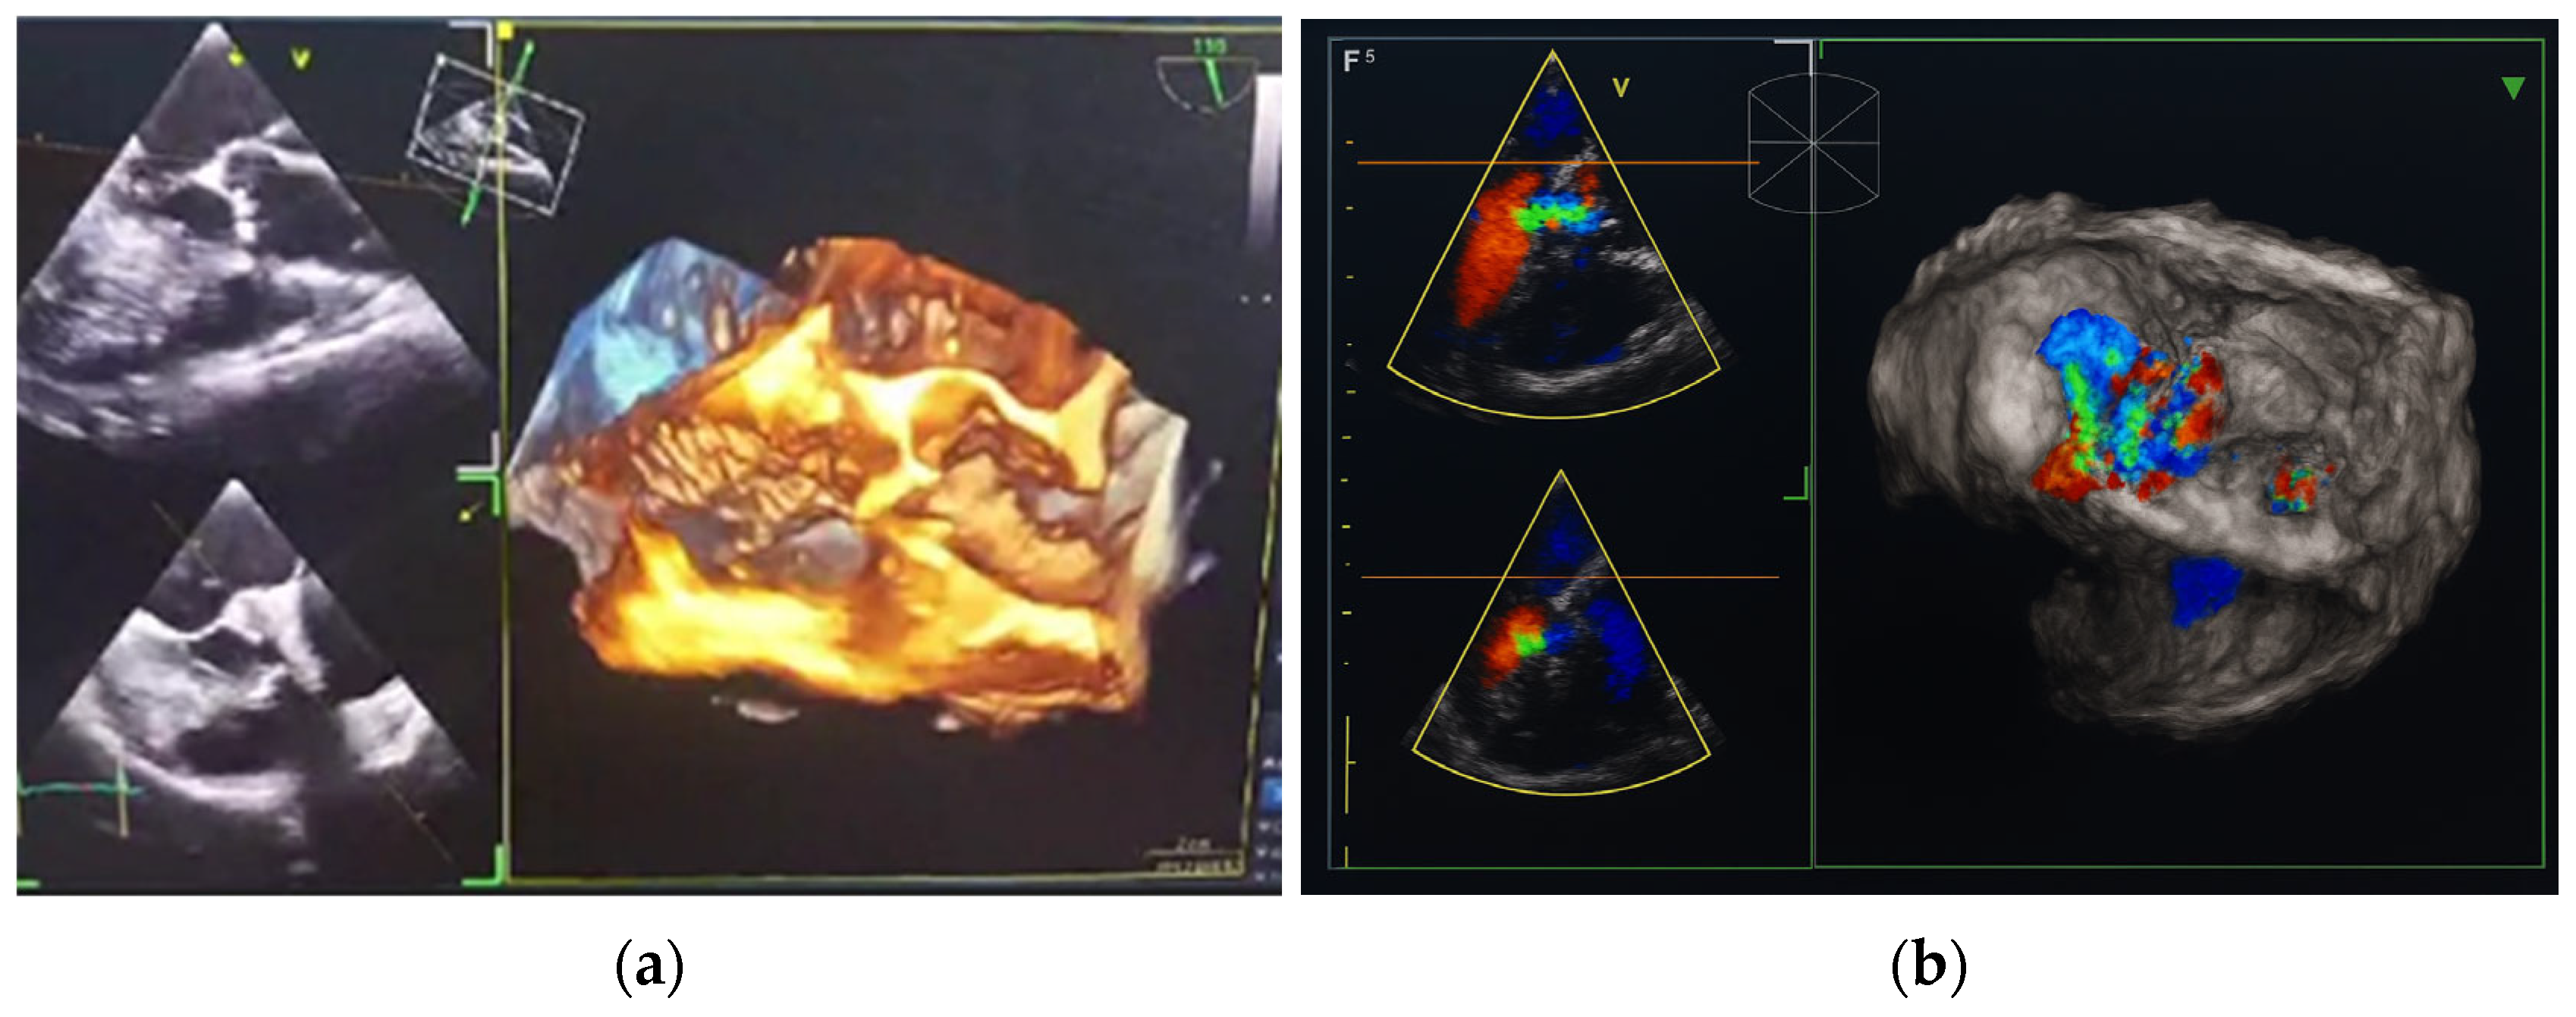

In October 2024, the patient was admitted to our Division of Rheumatology and Immunology due to exacerbation of her underlying overlap syndrome, demonstrating moderate to high disease activity: Disease Activity Score 28-ESR was 4.95 and Systemic Lupus Erythematosus Disease Activity Index was 6. Clinical symptoms included continuous moderate chest discomfort and worsening dyspnea upon exertion. She denied gastrointestinal or respiratory complaints, fever, or systemic signs of infection. Her long-term pharmacotherapy regimen included prednisone 7.5 mg/day, pantoprazole 40 mg/day, atorvastatin 20 mg/day, cholecalciferol 20,000 IU weekly, furosemide 40 mg/day, and lercanidipine 10 mg/day. Vital signs on admission were stable: blood pressure 140/90 mmHg, heart rate 76 bpm, and temperature 36.7 °C. Cardiovascular auscultation revealed a grade 2/6 systolic murmur over the precordium. Musculoskeletal examination was notable for bilateral wrist synovitis, bilateral shoulder pain with restricted range of motion, right knee arthralgia with limited mobility, and fixed flexion deformities of the right-hand fingers and left elbow. There was no clinical evidence of peripheral edema. Laboratory evaluation revealed: leukocytes 6500/µL, hemoglobin 88 g/L, platelets 188,000/µL, C-reactive protein (CRP) 11.7 mg/dL, erythrocyte sedimentation rate (ESR) 50 mm/h, hypocomplementemia (low C3 and C4), serum urea 4.9 mmol/L, and serum creatinine 144 µmol/L. Immunological testing showed negative RF and ACPA. Antinuclear antibodies (ANA) were positive at a titer of 1:160 with a homogeneous nuclear staining (AC-1 pattern). Anti-dsDNA was markedly elevated (86 IU/mL), and antiphospholipid antibodies (aPL), including lupus anticoagulant (LA), were triple positive. All other extractable nuclear antigens tested negative. High-sensitivity troponin I was elevated (84.0 ng/L), whereas N-terminal pro b-type natriuretic peptide (NT-proBNP) remained within normal limits (68.5 ng/L), and ECG findings were unremarkable. Due to persistent anemia, dyspnea, and dysphagia, repeat esophagogastroduodenoscopy was performed, confirming histologically proven erosive Helicobater pylori-negative gastritis. Repeat MSCT coronary angiography again ruled out acute coronary syndromes. Repeat TTE revealed a degenerative bicuspid aortic valve with a rudimentary left coronary cusp and moderate AR (aortic valve area: 2.4 cm2; vena contracta: 4 mm). Transesophageal echocardiography (TEE) confirmed these findings and offered a more detailed evaluation of valvular morphology and the severity of AR (Figure 2 and Figure 3).

Figure 2. Transesophageal heart ultrasound 2D imaging: (a) degeneratively changed bicuspid aortic valve with rudimentary left coronary cusp (red arrow). (b) 2D visualization of moderate aortic regurgitation in the context of a pathologically altered aortic valve.